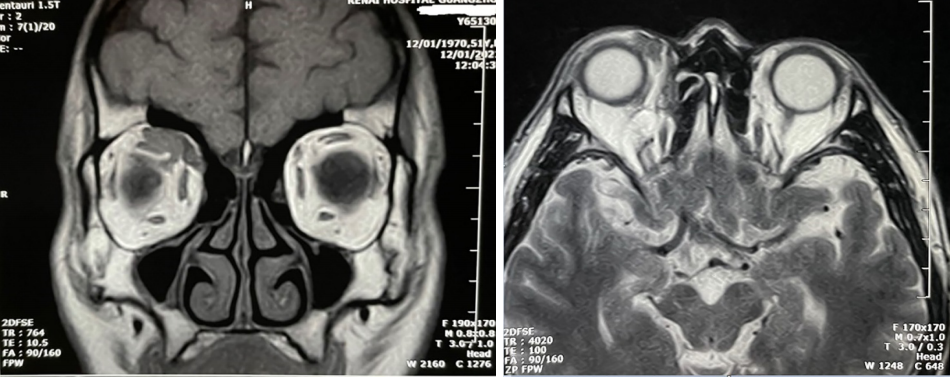

2.2 影像学特征

所有患者行CT或/和MRI检查,C T检查可见病变部位呈中等密度的软组织块影,密度较均匀,未见明显骨质破坏。MRI检查显示肿物呈“铸造样”,未侵犯眼球内结构,信号均匀,T1加权成像(T1-weighted imaging,T1WI)多呈中等信号,T2加权成像(T2-weighted imaging,T2WI)多呈稍高或等信号(图1)。

图1 MALT淋巴瘤患者MRI表现:眶上方可见软组织影,T1WI病变呈中等信号,信号较均匀,呈“铸造样”,眼球内未见侵犯

Figure 1 Images of MALT lymphoma: the lesion located upper the orbits, T1WI image of MALT lymphoma showed isointensity signal and “casting” sign, no intraocular invasion was observed

MALT淋巴瘤是最常见的眼眶淋巴瘤[7-8],常见于中老年人,本研究中以男性多见,平均年龄为55.4岁。本病发病缓慢、病程为数月至数年不等,呈惰性表现,对放疗敏感,较少发生转移,10年生存率高。多为单眼发病,本研究中65例为单眼,6例为双眼。有研究[9]报道,鹦鹉热衣原体感染和自身免疫因素可能是引起眼眶淋巴瘤的病因。对于MALT淋巴瘤病因的推测有很多,需要进一步探讨。肿瘤可发生于眶内任何部位,多位于眶上部及眶前部,常累及泪腺[10]。本研究38例位于眶上方,20例位于眶前部,13例位于眼眶其它位置,累及泪腺者4 5例。早期一般无明显症状,主要表现为局部肿块或轻度眼球活动受限,随着肿物逐渐增大,可出现眼球突出、异物感、复视及眼球活动严重受限等症状。眼眶淋巴瘤可为弥漫性病变也可为局限性病变,弥漫性病变多包绕眼球呈铸形生长,一般不导致眼球、眼外肌及眶骨等解剖结构的移位变形,不伴骨质破坏。MALT结外边缘区B细胞淋巴瘤在CT和MRI上常呈“铸造样”表现,不引起骨质破坏,病程较长者可出现骨质吸收变薄,罕见突破眼球壁向眼内生长[10]